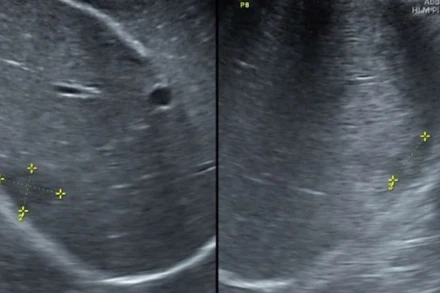

Đến khám vì đau dạ dày, tá hỏa phát hiện có sán lá gan lớn

Đau âm ỉ vùng thượng vị, nghi ngờ bệnh đau dạ dày nên bệnh nhân đến viện khám thì được phát hiện có sán lá gan lớn trong ổ bụng.